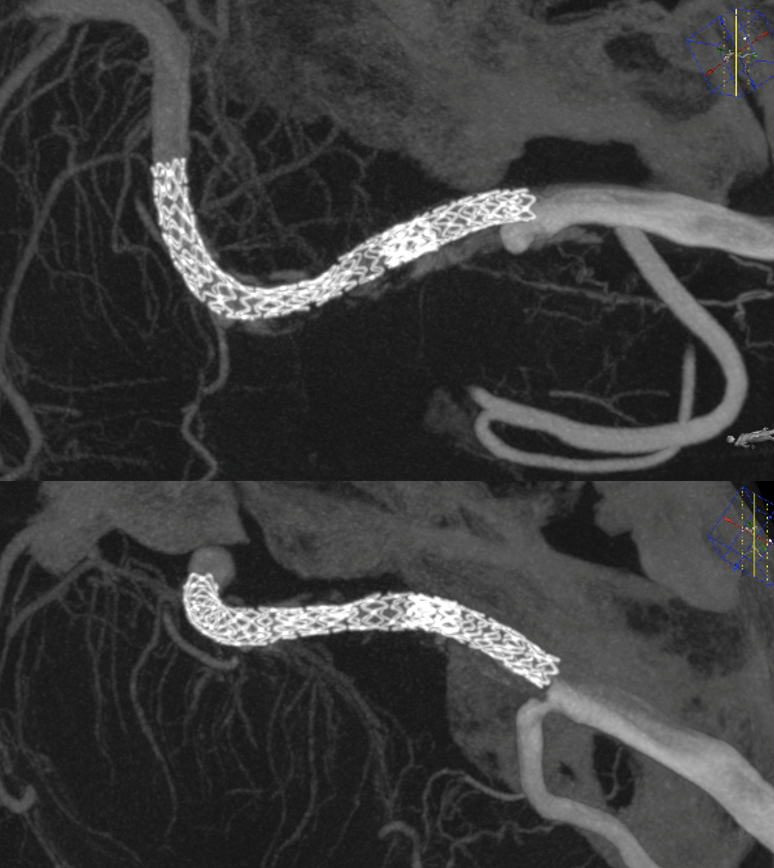

Vaso-CT (22 cm FOV protocol, 20 seconds acquisition, 50% contrast manual injection – 250 mg/ml, reconstructed with 50% FOV and 5123 matrix). We can see a stenosis at the origin of the PICA due to snowplough effect of the inflated balloon on the plaque — this is quite acceptable. With complete coverage of the PICA the result could be bad indeed. Precision matters a lot.

Laser-cut balloon-mounted stents make it easier to leave the PICA alone – critical given what you see below. The best choice in our opinion.